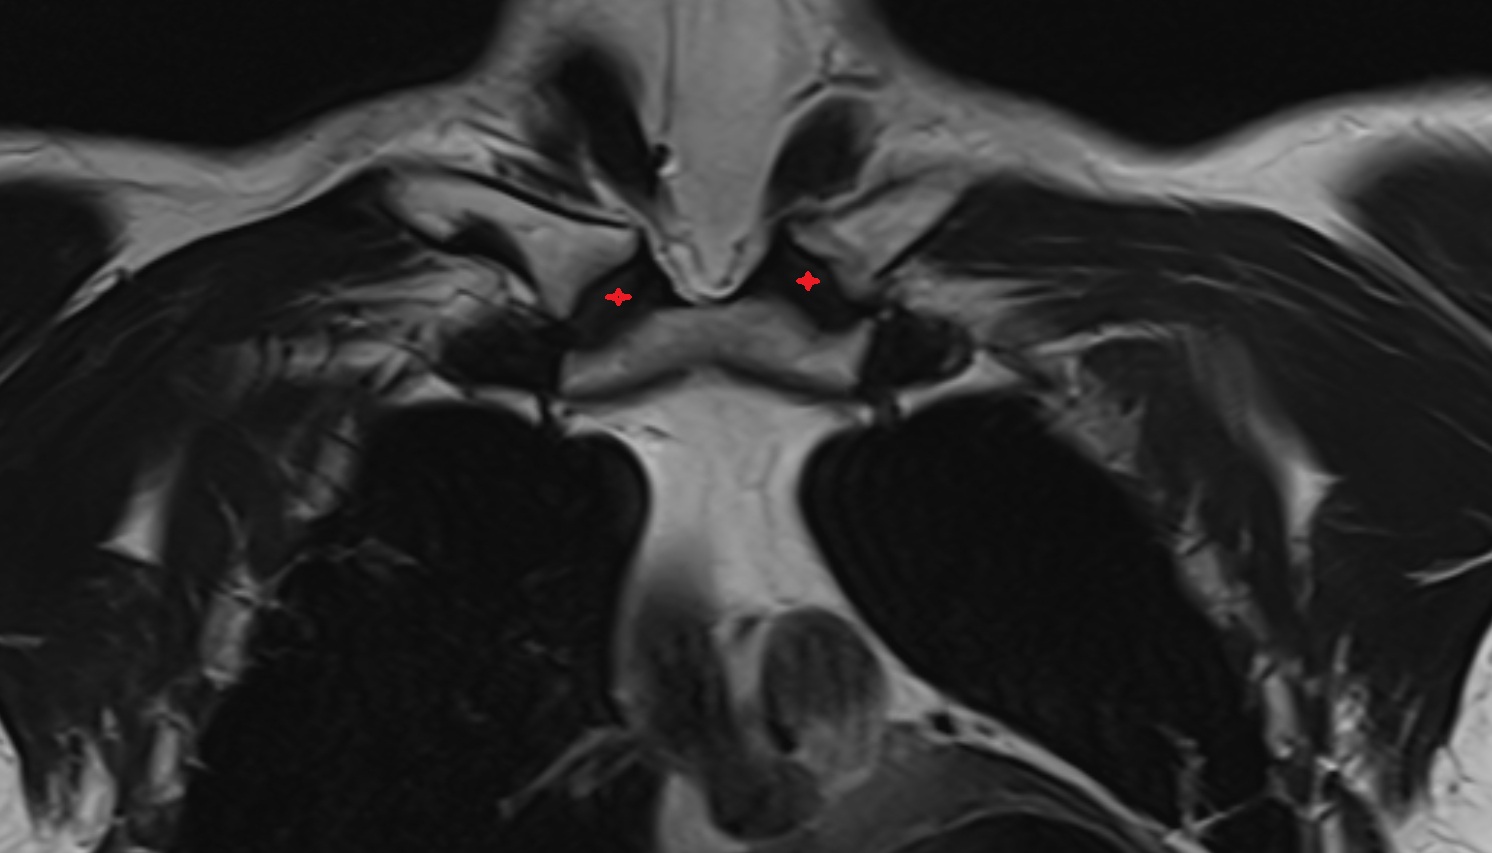

- Carotid bifurcation

- Common carotid artery

- Internal carotid artery (cervical part)